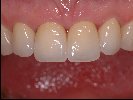

- Mit handgeschichteten Faceten aus Keramik ist es möglich einen Zahn naturgetreu wiederherzustellen